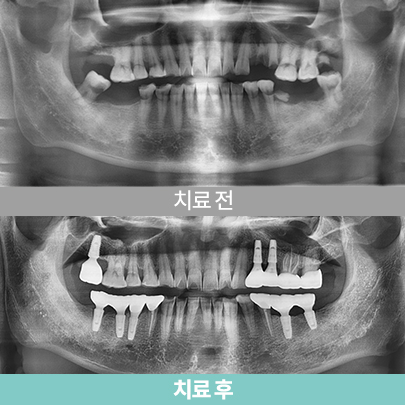

- 골조건을 고려한 All-on-4 설계, 치료 후 5개월

- 심미보철

- 심미보철

- 상·하악 풀마우스 임플란트

- 골조건을 고려한 All-on-4 설계, 치료 후 5개월

- 심미보철

- 심미보철

- 상·하악 풀마우스 임플란트